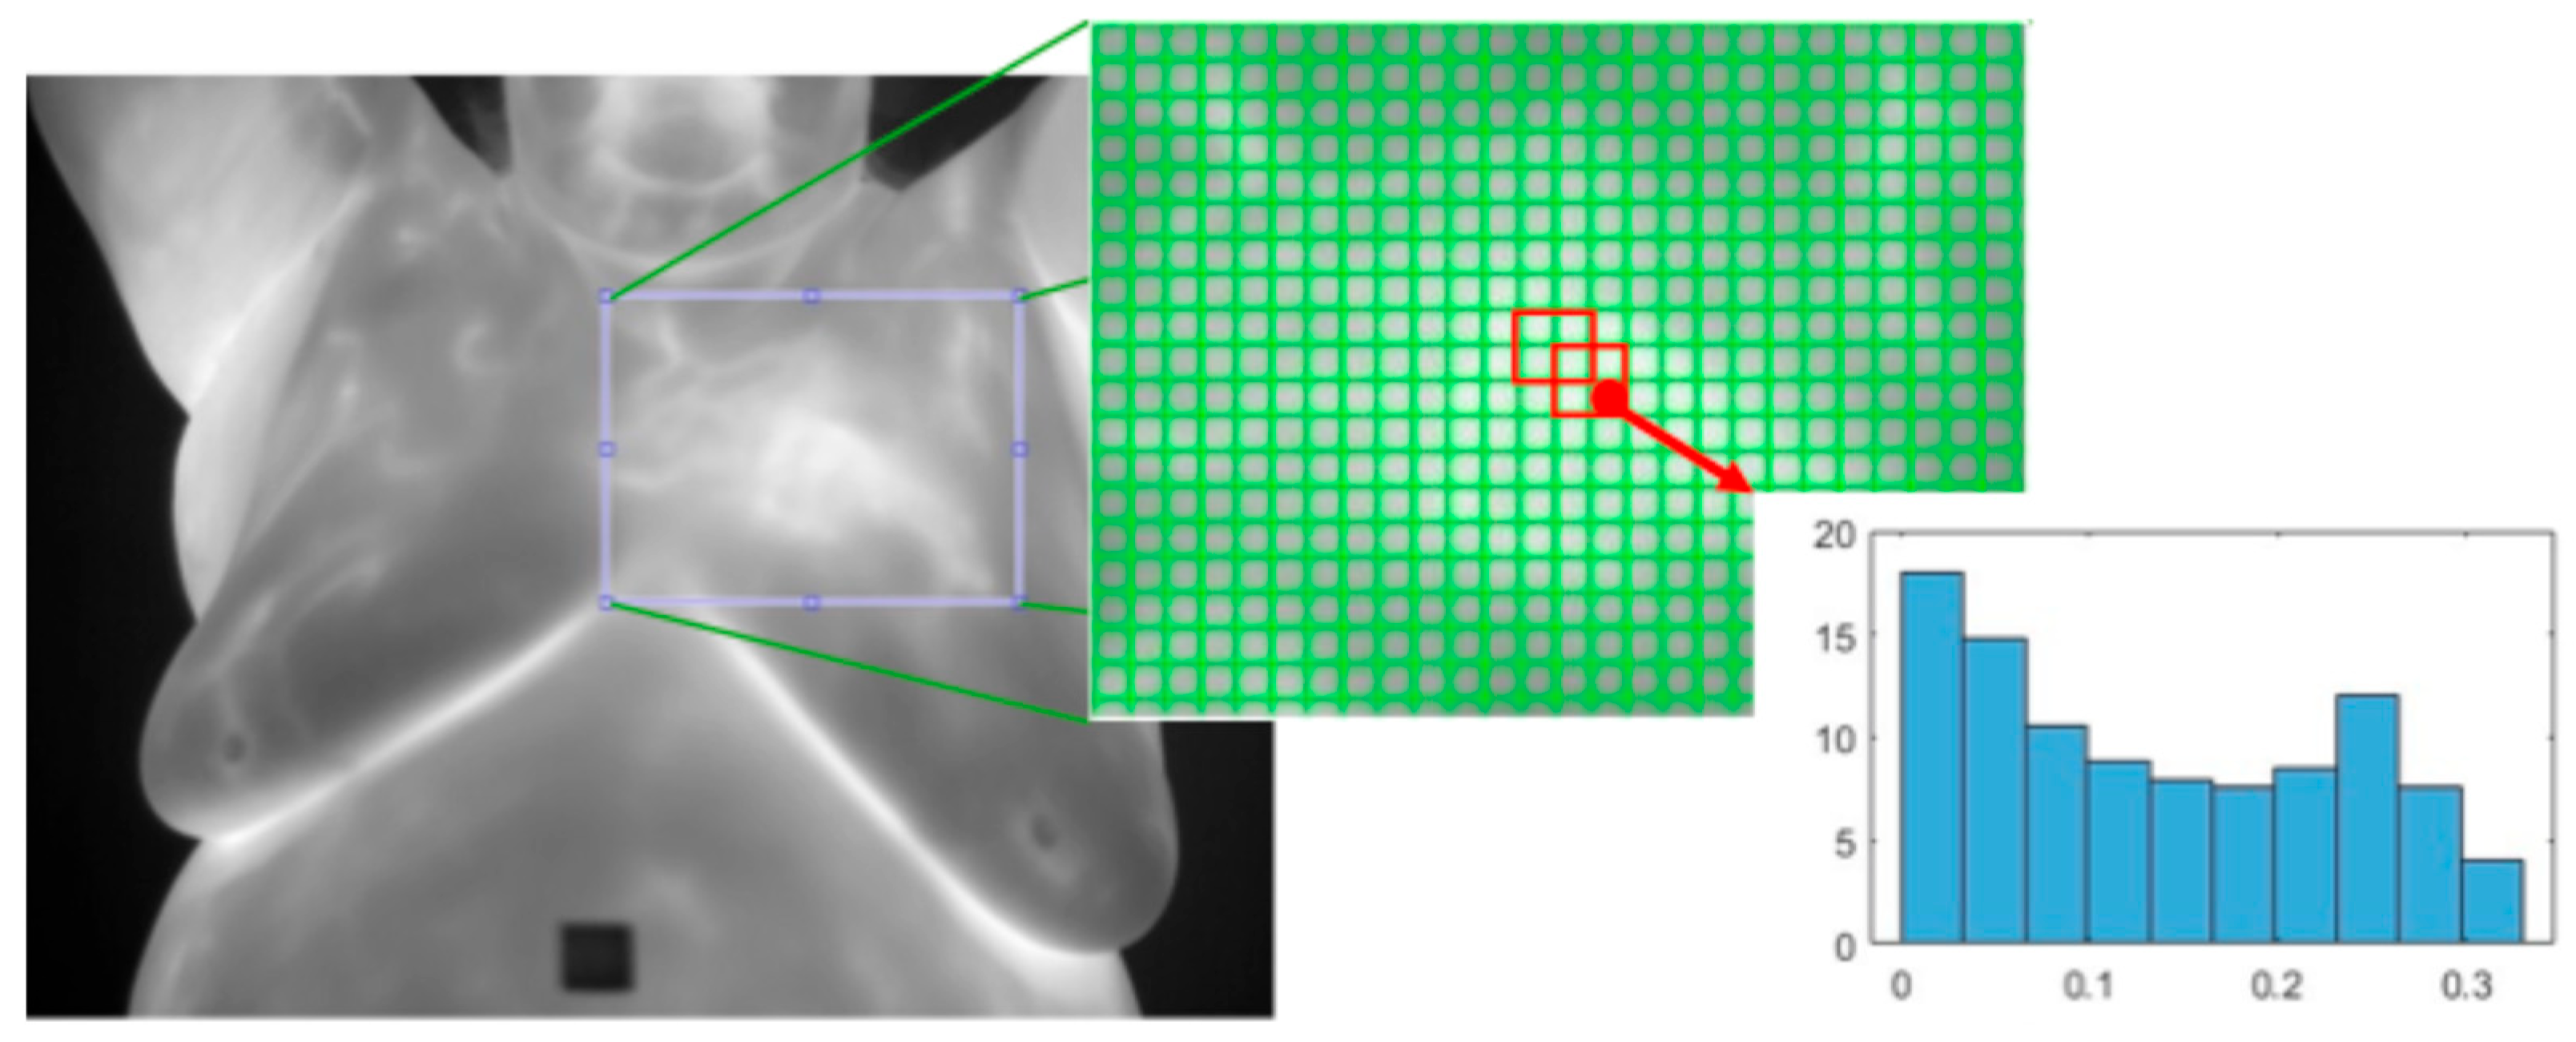

- Histogram of Oriented Gradients (HOG): This [33] is a texture feature extractor that is also applied to the detection of objects in images. An image is split into non-overlapping cells of a predefined size. Regions are defined as a fixed number of cells and may overlap. The gradient is calculated for each pixel and the histogram of all the gradients within each cell is calculated. All the cell histograms of gradients within a region are normalized and concatenated into a single vector and then all the region vectors are concatenated into one vector. See Figure 11.